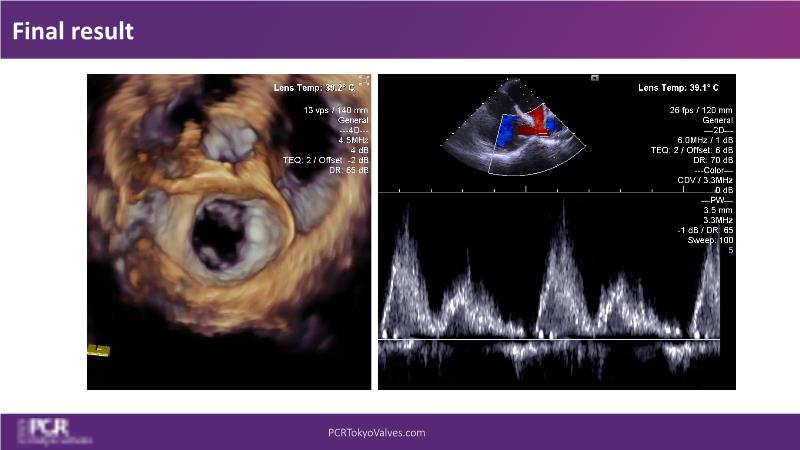

Watch this session to get an overview of a new TEER device, follow the step-by-step procedure related to initial experiences with this device for a Japanese patient with degenerative mitral regurgitation, learn about the latest data from RCT and registries, and follow discussions of challenging TEER cases!

- To understand how novel TEER device provides new possibilities in TEER

- To learn procedural step-by-step of novel device